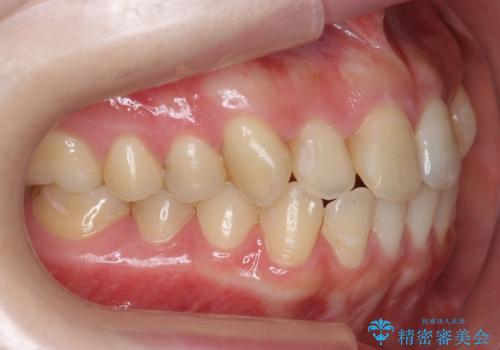

犬歯のねじれ 上の歯が引っ込んでいる

- 前歯の並びを気にして来院。

インビザラインで、上の前歯をやすり掛けして並べました。

- 2年8ヶ月